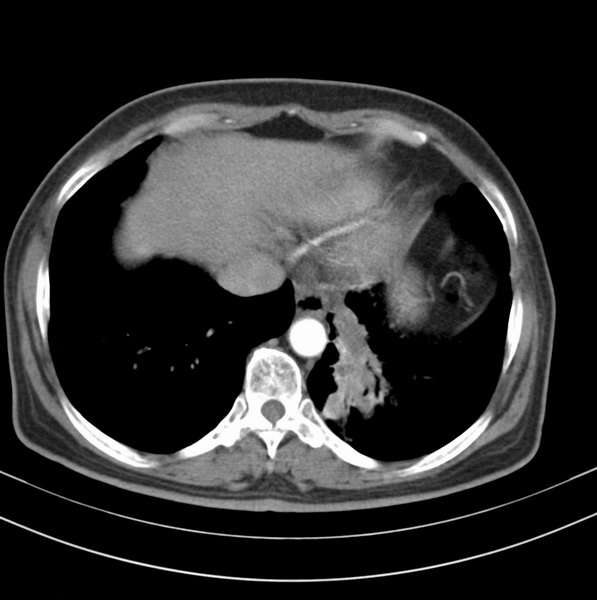

女、63

咳嗽、胸痛四个月

考虑左下肺中央型肺癌

支持左下中央型肺癌伴阻塞性炎症不张。

包绕左下肺基底段的不规则的软组织肿块,段支气管腔变形、狭窄及阻塞性炎症,病变区不规则强化,又是老年女性支持楼上看法。

典型病例:左下肺基底段中央型肺癌,相应支气管狭窄并阻塞性炎症